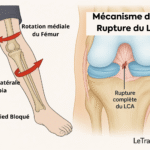

Lésions méniscales ou ligamentaires non traitées

Une lésion du ménisque, même ancienne, peut se réveiller en position allongée. Le genou devient douloureux lors d’un mouvement involontaire la nuit. Les douleurs ligamentaires post-traumatiques sont aussi fréquentes après une entorse mal soignée.